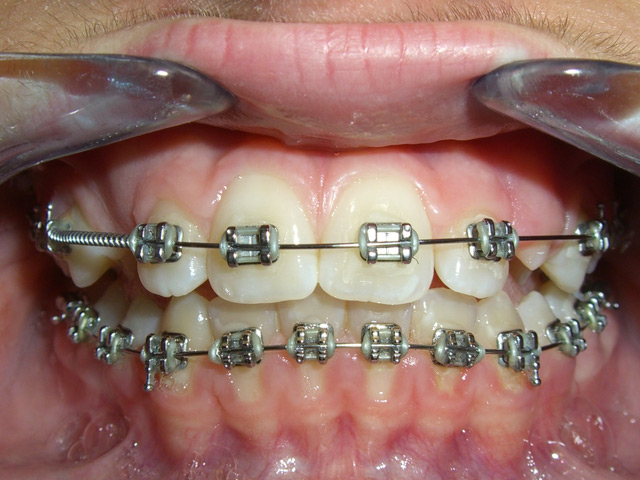

Gli apparecchi fissi sono costituiti da attacchi in metallo o in ceramica che vengono applicati direttamente sui denti mediante resine adesive. Nelle fessure degli attacchi vengono inseriti degli archi i quali generano forze ortodontiche idonee a provocare il movimento dei denti.